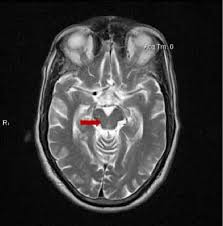

The single best MRI marker per this study was the area of the midbrain, the fat, V-shaped structure indicated below: